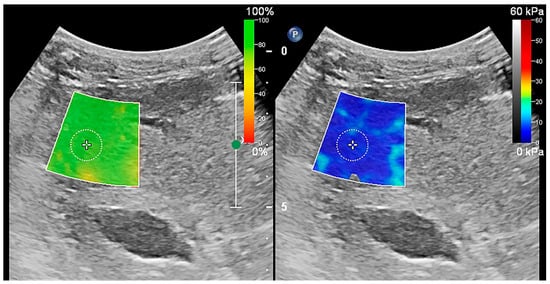

3.2. Influence of Anesthesia on the Measurement of Liver Stiffness

Anesthesia significantly altered the stiffness of the liver in healthy dogs (Table 2 and Figure 4). The stiffness was significantly higher in the anesthesia state than in the awake state, both on the right and on the left liver lobes (p < 0.01 for the right liver lobe, p < 0.01 for the left liver lobe). The color changes in the stiffness map reflect the impact of anesthesia on liver stiffness in healthy dogs. After anesthesia, the color of the stiffness map shifted from a uniform light blue to a mixture of blue and green (Figure 5).

Figure 5. 2D-SWE measurement in awake and anesthesia states state. (a) 2D-SWE measurements in the awake state (b) 2D-SWE measurements in the anesthesia states state. The color changes in the stiffness map reflect the effect of anesthesia on the liver stiffness. Before anesthesia, the stiffness map displayed a uniform blue color, while it exhibited a mixture of blue and green colors in the anesthesia state.